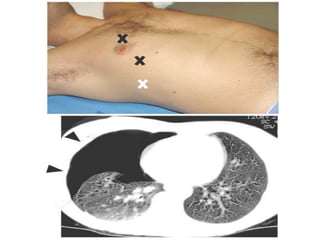

Scanning Positions for

Chest Sonography in ICU

Tissue pattern representative of Alveolar

Consolidation

Presence of hyperechoic punctiform

imagesrepresentative of air bronchograms

Pleural

effusion

Lower lobe